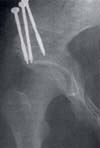

Fig. 1. Cadera displásica

Fig. 2. Postoperatorio osteotomía de Steel.